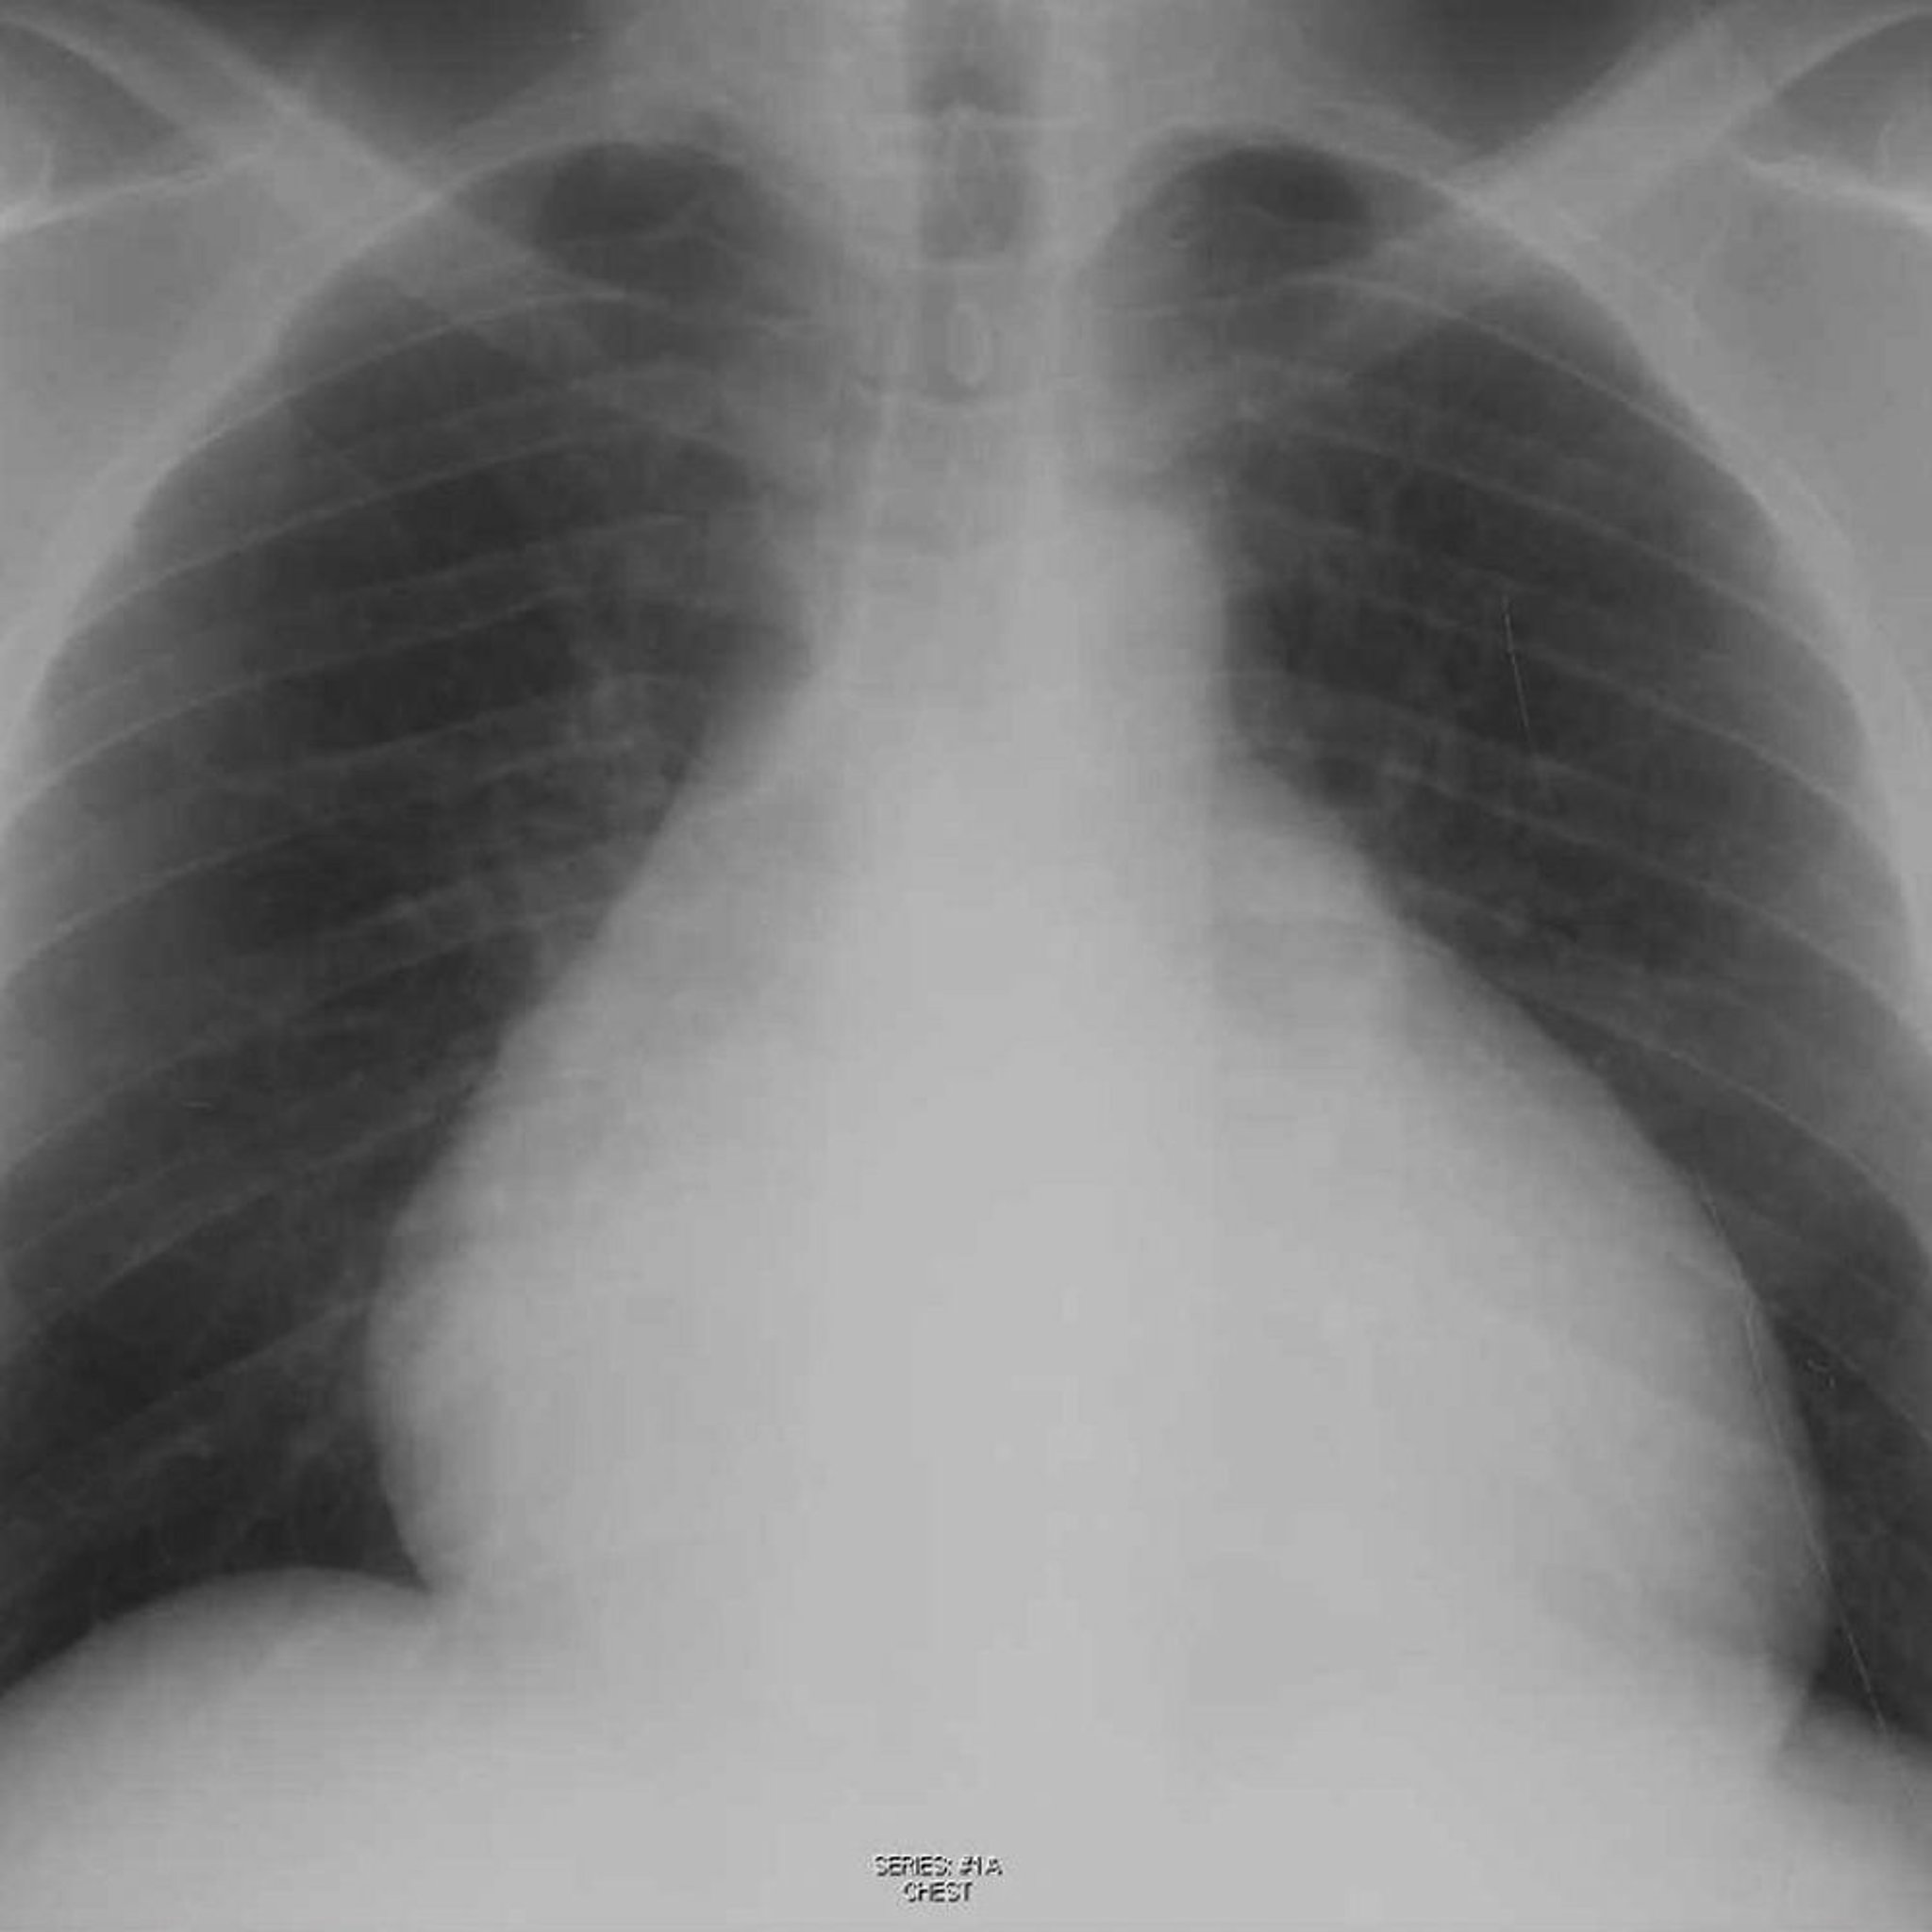

Radiografia do tórax de um paciente com derrame pericárdico

Essa radiografia mostra silhueta cardíaca aumentada em um paciente com derrame pericárdico.